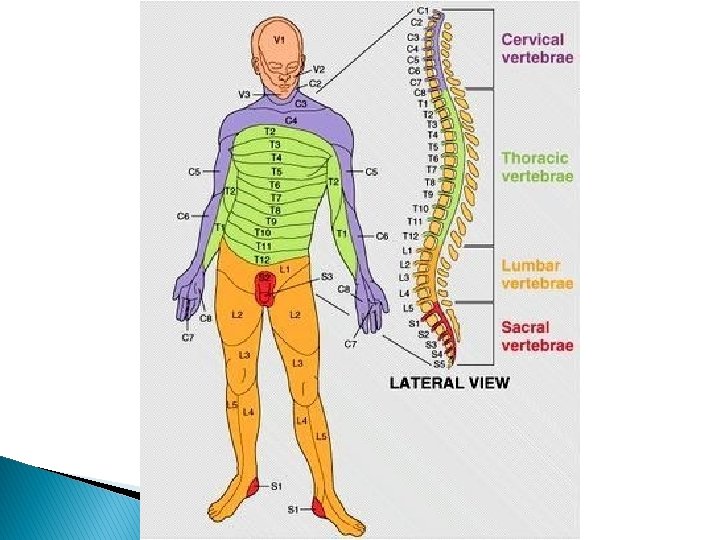

ÚTK: Mænutaugar � Mænutaugarnar eru nefndar eftir þeim hryggjaliðum sem þær ganga út á milli: ◦ ◦ ◦ 8 á hálssvæði (cervical) 12 á brjóstsvæði (thoraic) 5 á lendarsvæði (lumbar) 5 á spjaldhryggsvæði (saccral) 1 á rófubeinssvæði (coccygeal)